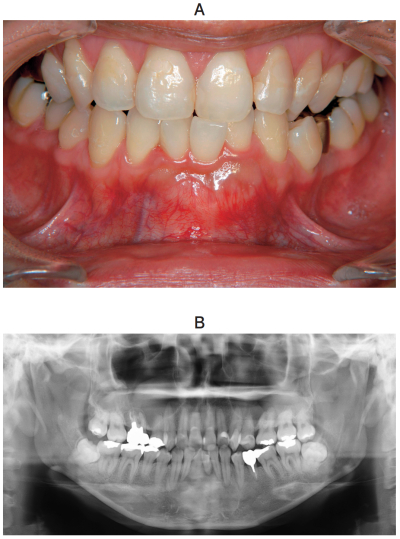

34歳の女性。下顎前歯部歯肉の膨隆を主訴として来院した。3か月前に気付いたが疼痛がないためそのままにしていた。膨隆は徐々に増大しているという。口腔内写真、エックス線写真、CT及び生検時のH-E染色病理組織像を別に示す。

診断名はどれか。1つ選べ。